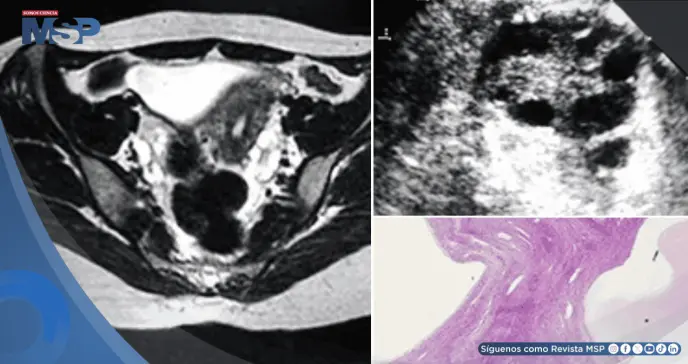

La hormona FSH, que regula la función ovárica, aparecía extremadamente elevada, indicando que los ovarios habían dejado de funcionar. Simultáneamente, se detectó mal funcionamiento tiroideo con anticuerpos elevados que confirmaban una enfermedad autoinmune del tiroides.

El escenario que emergió fue el de una falla múltiple del sistema endocrino. La elevación extrema de la hormona FSH señalaba una insuficiencia ovárica prematura, explicando tanto la ausencia de menstruación como los sofocos típicos de la menopausia.

La inflamación tiroidea con anticuerpos elevados correspondía a una tiroiditis autoinmune. Los síntomas de fatiga, baja presión arterial y las alteraciones en los electrolitos sugerían además un compromiso de las glándulas suprarrenales, que posteriormente se confirmó con pruebas específicas.